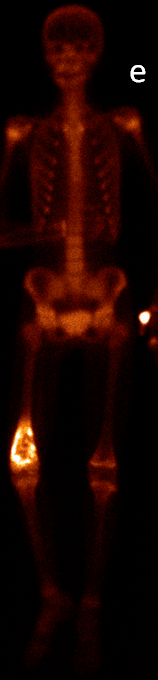

21.2.3. Primary bone tumors

In cases of primary bone tumors, three phase scintigraphy can help to determine the dignity of equivocal bone lesions. Benign lesions do not show typically increased activity in the early phases, and even if there is a detectable late phase activity, it is moderate (except for osteoid osteoma, osteoblastoma, fibrotic dysplasia and aggressively growing bone cysts, or lesions that are associated with pathologic fractures.) Malignant tumors (osteosarcoma, Ewing sarcoma) as opposed to benign tumors, have an increased blood supply and a more intense osteoblast activity. (Figure 6.)

6. Osteosarcoma in the right femur. Three phase bone scintigraphy, planar anterior images. Perfusion phase acquisitions (a), summation (b), early blood pool phase (c), late phase (d), whole body scan (e).

Scintigraphy is also helpful in determining any skip lesions and bone metastases that are normally associated with malignant tumors. It is also useful in monitoring preoperative chemotherapy, and tumor recurrence. In osteosarcoma, because of the tumor’s osteoid production, it is also possible to detect soft-tissue metastases (e.g.: lung metastases). Tumor-specific nuclear medicine examinations, such as FDG-PET are useful for the staging and re-staging of the tumors and in monitoring chemotherapy. Uncertain processes can be differentiated by FDG-PET, since low grade sarcomas have no or minimal glucose metabolism, while high grade sarcomas have high glucose metabolism. Concerning benign tumors, scintigraphy is basically 100% sensitive for osteoid osteoma. Its nidus shows an intensive, dot-like activity increase in all three phases of the examination. Since the activity accumulation in osteoid osteoma is so intense, isotopic methods (intraoperative scintigraphy or gamma probe) can be used as a guiding tool during surgery.